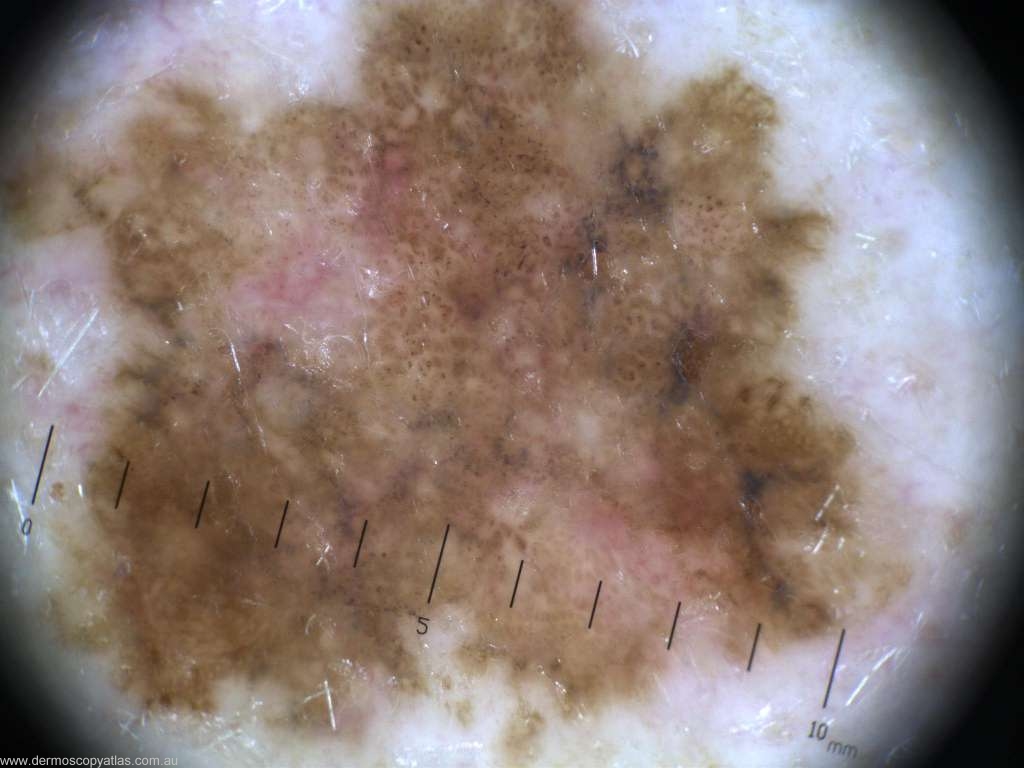

Case 6 47 year old male. Routine check. No history. R upper arm.

Question: Which diagnosis is correct? Consider Melanoma in situ, Seborrhoeic keratosis, Melanoma invasive, Junctional nevus, Pigmented BCC, Dysplastic nevus, LPLK and Pigmented IEC

Answer: Histology: L1 (in-situ) superficial spreading melanoma